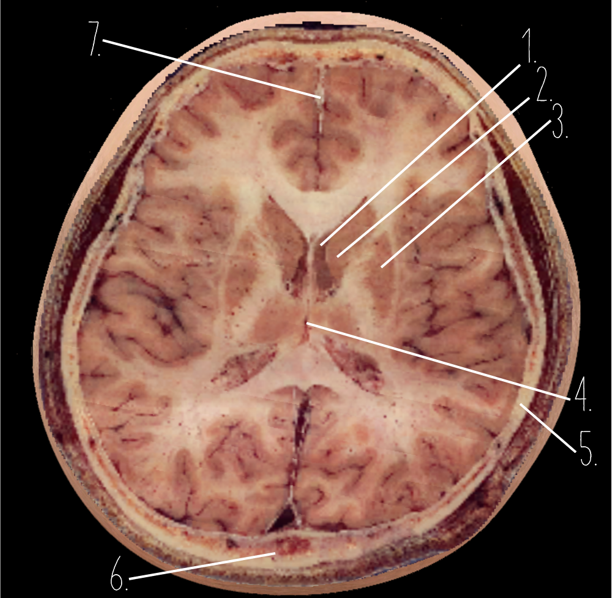

1?

Anterior Horn of the Lateral Ventricle

2?

Putamen

3?

Thalamus

4?

Internal Occipital Protuberance

5?

Cerebellar Vermis

6?

Third Ventricle